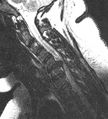

الانزلاق الغضروفي العنقي

يحدث الانزلاق الغضروفي العنقي، غالبًا بين الفقرات العنقية الخامسة والسادسة (C5–6) والسادسة والسابعة (C6–7). هناك قابلية متزايدة بين المرضى الأكبر سنًا (60+) للفتق في الجزء العلوي من العنق، وخاصة في الفقرات العنقية الثالثة والرابعة.[23] قد تظهر أعراض الانزلاق الغضروفي العنقي في الجزء الخلفي من الجمجمة والعنق وحزام الكتف ولوح الكتف والذراع واليد.[24] قد تتأثر أعصاب الضفيرة العنقية والضفيرة العضدية.[25]